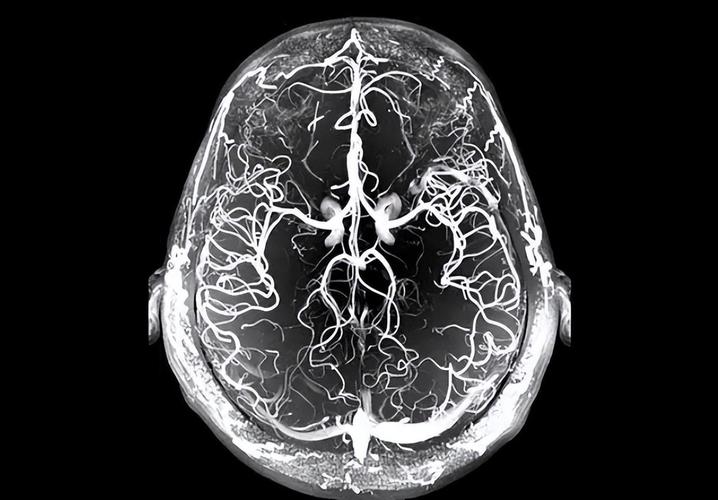

- 大血管闭塞?:医生可能会安排磁共振血管成像(MRA)或CT血管造影(CTA),查看颅内大血管是否有堵塞或严重狭窄,这是决定是否进行静脉溶栓或机械取栓的关键。